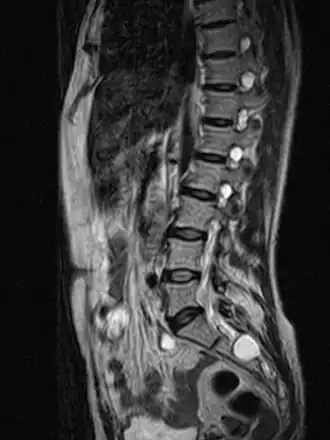

Un kyste de Tarlov (KT) ou kyste périneural, est une dilatation locale de l'espace sous-arachnoïdien se formant au contact d'une racine nerveuse, le plus souvent sacrée, dans la zone de transition entre arachnoïde et périnèvre (membrane externe du nerf). Il est fréquent et le plus souvent asymptomatique, mais peut parfois causer des symptômes neurologiques : on parle alors de maladie de Tarlov.

Le kyste de Tarlov est le plus souvent asymptomatique et découvert fortuitement lors du bilan d'imagerie d'une lombosciatique[5]. Cependant le kyste en lui-même peut être une cause de sciatique, voire lorsqu'il est situé au niveau sacré de troubles vésicosphinctériens (mictions impérieuses, dysesthésie anale...)[5]. Chez la femme, le kyste de Tarlov peut être la cause d'un syndrome d'excitation génitale persistante[6].

Quel que soit le système de classification, la définition d'un kyste de Tarlov est histopathologique car elle nécessite la présence de fibres de racines nerveuses de la colonne vertébrale dans la paroi du kyste ou dans sa cavité. Les kystes de Tarlov sont définis comme des lésions sacciformes, remplies de liquide cérébrospinal (LCS), situées dans l'espace extradural du canal spinal sacré et formées à l'intérieur de la gaine de la racine nerveuse au ganglion de la racine dorsale.